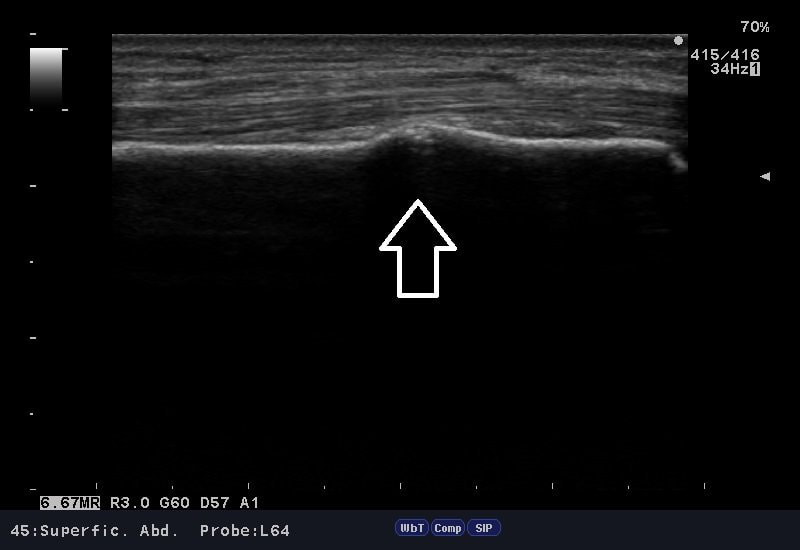

自転車で転倒した際、左手を突いた時に、手首を痛めたと御来院。

問診、視診、触診、そしてエコー検査。

結果「橈骨遠位端部骨折」の部位を確認。

腫れ具合から骨折の有無はある程度予想できますが、エコー検査は骨折の箇所を的確にその場で確認でき、骨癒合を促進させるマイオパルス(MYO PULSE)という治療器で、治療を行えるので強い味方です。